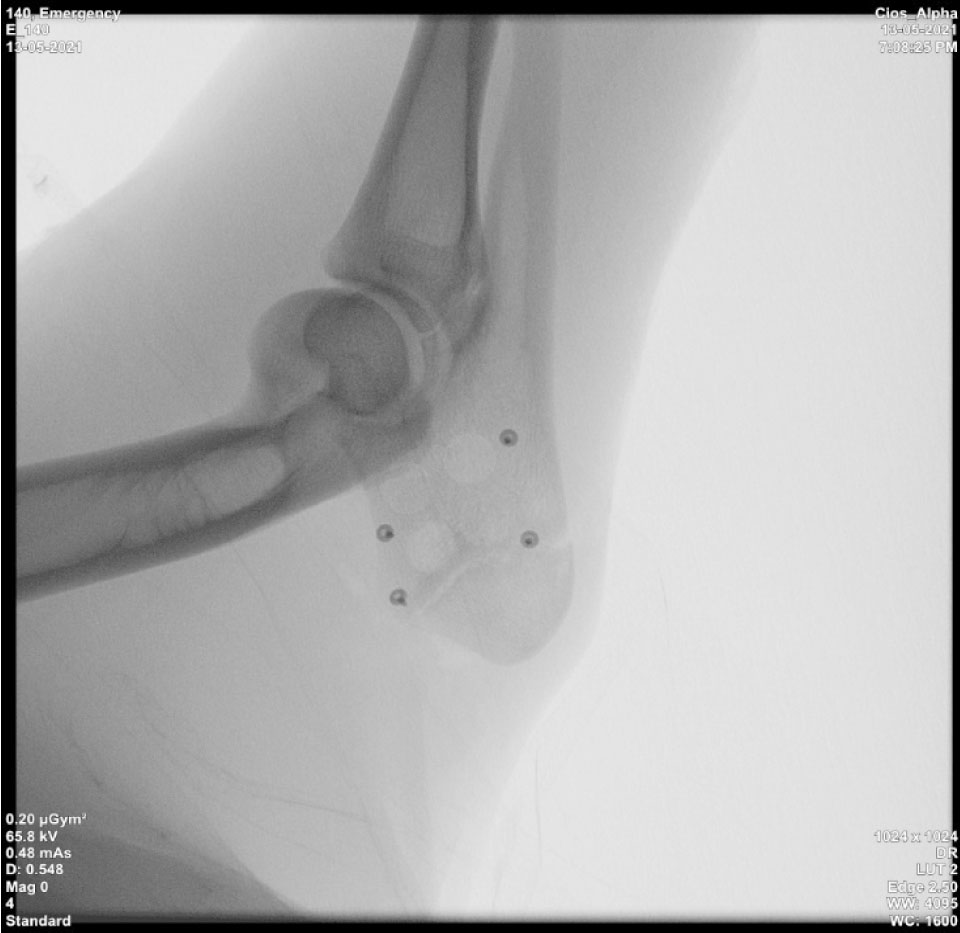

После хирургического этапа проводили рентгенологический прицельный контроль в каждой области имплантации (рис. 7).

Рис. 7. Контрольная рентгенограмма локтевого отростка сразу после операции. Визуализируются 4 трепанационных отверстия, титановые пины, фиксирующие коллагеновую мембрану